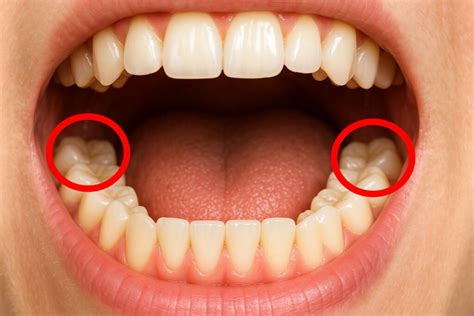

Tipos de Cordales

Las muelas del juicio pueden clasificarse según su posición y estado de desarrollo dentro de la mandíbula:

- Erupcionados: Han salido completamente de la encía y están bien alineados.

- Impactados: No logran erupcionar y están cubiertos por la encía o el hueso.

- Parcialmente Erupcionados: Han erupcionado parcialmente.

- Angulados: Intentan salir, pero están en una posición incorrecta.

- Ausentes: No se desarrollan en absoluto.

- Supernumerarios: Algunas personas pueden tener más de cuatro (aunque es raro).